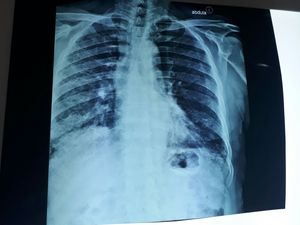

What is your diagnosis

Pneumonia with old TB(maybe) , need more imaging

No just air in the diaphragm

Are you sure? So what are the consolidations in the right lung?